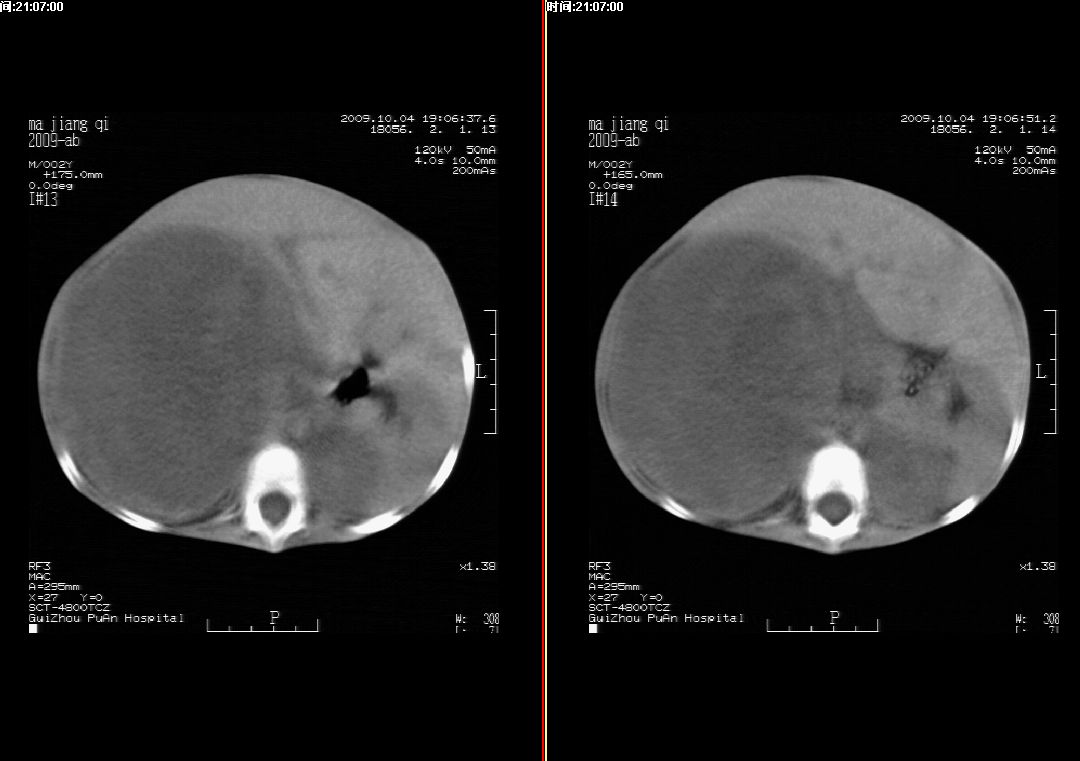

右肾巨大囊性占位病变,其内密度不均,正常肾结构消失,肝脏,肾上腺及肠管等受压移位。双肺内多发大小不等的结节及块状影。考虑右肾母细胞瘤伴双肺多发转移。

肾母细胞瘤(wilms),系儿童最常见的恶性肿瘤,好发于3岁以下儿童,瘤体较大,主要由胚胎性肉瘤样细胞和上皮样细胞构成,临床以腹部肿块;血尿和高血压为主要体征。

ct表现:密度不均匀的大肿块存在;出血和坏死。与神母鉴别点:wilms易向颅脑转移,而神母易往肺转移。

ct表现:密度不均匀的大肿块存在;出血和坏死。与神母鉴别点:wilms易向肺转移。而神母易往颅脑转移.